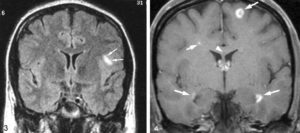

- «Пальцы Доусона». Это демиелинизация (разрушение миелиновых волокон) белого вещества ГМ. Патологические образования имеют продолговатую форму и располагаются вдоль малых мозговых вен перпендикулярно к боковым желудочкам.

- Множественность поражений и их локализация в перивентрикулярной области.

Для демиелинизации характерны очаги овальной формы, прозванные «пальцами Доусона». Пальцы Доусона характеризуют потерю миелина, оберегающего отростки нейронов в белом веществе мозга вдоль малых мозговых сосудов. Овальные бляшки служат одним из самых ярких признаков множественного склерозирования миелина, и возникают вследствие воспаления тканей, окружающих венулы.

- Распространение в месте подтверждается наличием более одного T2-очага (накопление контраста не обязательно) в двух из четырех отделов мозга:

- Перивентрикулярно(вблизи желудочков головного мозга).

- Юкстакортикально(вблизи коры головного мозга).

В белом веществе спинного мозга и в глубинных отделах головного выявляют бляшки РС различного количества и размеров. Характерным является их расположение по краям мозолистого тела, в ножках, стволе, мозжечке.

В типичных случаях в структурах головного мозга в режиме Т2-взвешенных изображений выявляют очаги повышенной интенсивности овальной формы от 2 до 20 мм вдоль тел и рогов желудочков, в мозолистом теле, реже — в белом веществе полушарий головного мозга, стволе, мозжечке. Свежие очаги хорошо визуализируются при контрастировании.